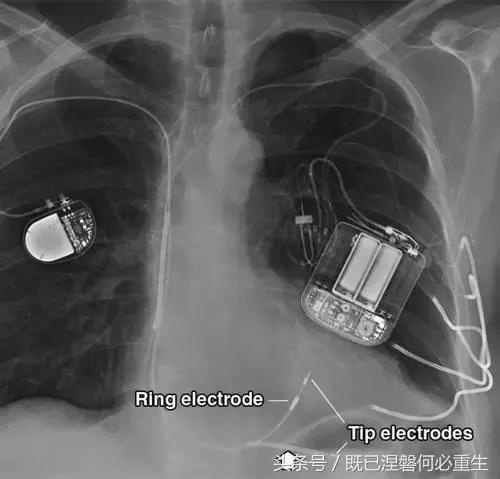

图 1A B 在75岁男性中植入式心律转复除颤器(ICD)的正常部件。

A,额叶胸片显示Medtronic(公司名字)单室ICD。 ICD的基本组件包括发生器,导线和围绕右心室(RV)导线的冲击线圈。 该系统还具有上腔静脉(SVC)中的冲击线圈,其可能不存在于所有系统中。 起搏器没有冲击线圈。 铅固定(见图8A)固定到胸部,并且可能或可能不在胸部X光片上可见。

B,引线通过头连接到发电机(黄色),其保持一个或多个连接端口。 所示系统需要三个端口(一个用于双极起搏或感测元件,一个用于RV休克线圈,一个用于SVC冲击线圈)。 正确放置的引脚将延伸超出连接器(见图9)。 制造商的标志和单个设备标识符的字体被反转,因为发电机被定向以允许在发生器口袋中适当的引线盘绕。 这种定位被设计成减少扭结的风险,这可能导致断裂。 有关制造商徽标的更多信息,请参见图4。

图。 3A 普通电极和电极导管固定在一个62岁的男人。A,额部胸片显示右侧的Medtronic单室起搏器和左侧的CPI(心脏起搏器公司)植入式心律转复除颤器(ICD)。 每个装置具有不同类型的双极右心室(RV)导联。 尖端电极位于两个RV引线的终端,而起搏器引线上的短的近端金属不透明是环形电极。 集成双极ICD引线使用RV冲击线圈作为其环电极(箭头)。 仅具有顶端电极和没有冲击线圈的引线是单极的,并且使用发生器的金属外壳作为等效的环形电极(未示出)。 左胸壁的曲线金属混浊是皮下阵列,其用于在需要大量能量去纤颤的患者中降低(改善)除颤阈值。 皮下阵列将更多的心室壁纳入冲击范围,比单独的休克线圈作用范围更广。

图。 3A 普通电极和电极导管固定在一个62岁的男人。B,电极的放大图像。 起搏器导线被主动固定并通过心肌中的螺钉尖保持在适当位置。 ICD导线被动地固定有射线可透射的尖齿。 胫骨陷入小梁骨内膜(或心房),并且导线变得锚定有纤维化的发展,这通常需要6周至3个月。